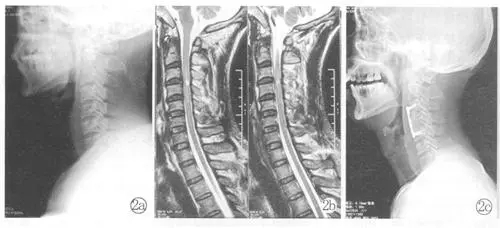

故事得从一个多月前的6月18日说起。那天,周阿姨因为颈部脊髓损伤被紧急送进医院。初来时,她的状况让人揪心:右侧手脚完全不听使唤,手指头连弯一下都困难,基本上只能躺在床上。面对这样的病情,黄朝霞主任带领团队迅速制定了详细的康复计划。